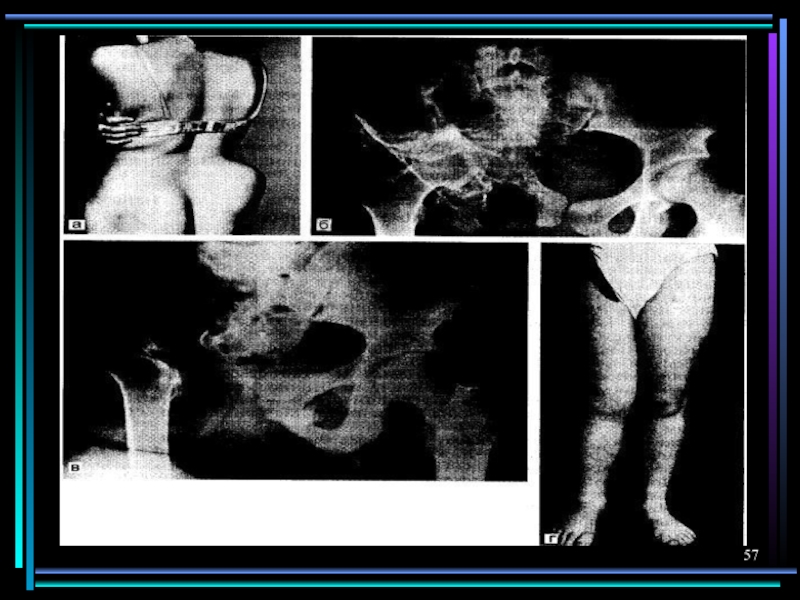

Слайд 52Поражение опорно–двигательного аппарата

Трихинеллез

Эхинококкоз

Цистицеркоз

Ангиомиозит скелетных мышц: резкие боли при движении, отек и

болезнен-ность при пальпации, ч/з 5 недель инкапсуляция личинок, ч/з несколько месяцев – начало обызвествления

2-3% кист локализуются в костях с развитием многочисленных пузырей в костном канале с асептическим некро-зом кости. Характерны спонтанные переломы без предшествующей боли. Вторично поражаются суставы.

Цистицерки локализуются в мышцах плечевого пояса и бедра. Не пальпиру-ются, боль отсутствует, ч/з несколько лет обызвествляются. Видны на R-грамме – до 1см.